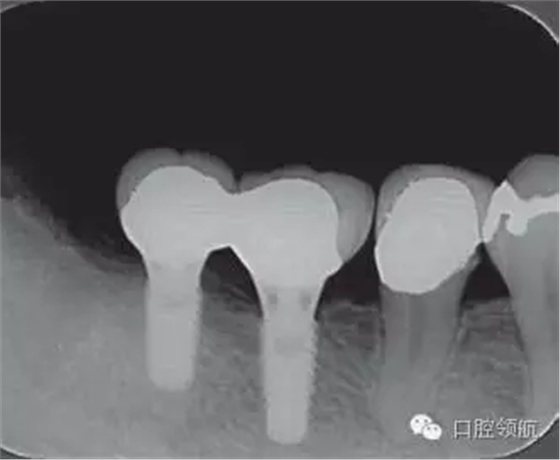

修復體安裝后的2003年1月復診時的X線片上,沒有發(fā)現(xiàn)種植體頸部有骨吸收現(xiàn)象,情況良好(圖2)。但是,2003年8月,因混合陶瓷樹脂部分修復體的破損而進行再制作時,發(fā)現(xiàn)有輕度的咬合疼痛以及舌側頸部的牙齦有輕壓痛。口內沒有觀察到該部位的牙齦紅腫。X線片可以觀察到(左下第6顆牙) 的種植體頸部有達到第4螺紋的骨吸收現(xiàn)象(圖3)。

圖2 沒有發(fā)現(xiàn)種植體頸部的骨吸收(2003年1月)